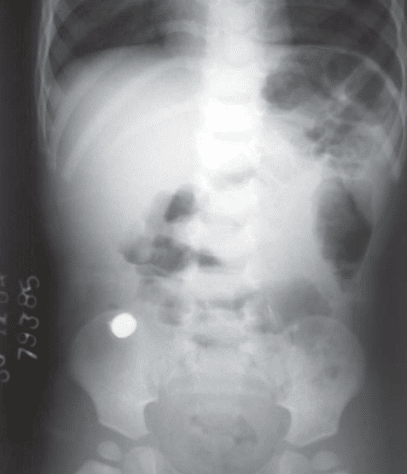

- إذا وصل للأمعاء الغليظة: حينها يطمئن الطبيب فهو في طريقه للخروج من الجسم.

- ممر الجهاز الهضمي هو ممر الأمان لأنه يعني تجاوز العملة المعدنية الجهاز التنفسي ووصولها للجهاز الهضمي وهنا يسهل التخلص منها عن طريق البراز بدون أي إجراءات أيا كان مكانها سواء في المعدة أو الأمعاء، وفي هذه الحالة لا يظهر على الطفل أي أعراض، حتى أن تنفسه يكون منتظم.

- و بخضوع الطفل لعمل أشعة “اكس” على البطن على أن يكون الطفل واقفا لتحديد مكانها فقط، خاصة أنها لن تتسبب في وجود أي مشكلة في الجهاز الهضمي، وأكد أنه لا يكاد يمر أسبوع إلا وقد تخلص الجسم منها.

- إذا علقت العُملة داخل موضع ما بالجسم ستظهر علامات على ذلك من العلامات القئ، وألم الصدر والبطن إذا كانت عالقة في المرئ أو المعدة. أما إذا علقت على جدار الأمعاء فقد تؤذي الجدار، ومن علامات وجودها في ذلك الجزء وجود صوت غريب عند إخراج البراز أو وجود نزيف معه. من الهام أن يلجأ الآباء إلى الطوارئ، وألا تتم محاولة إخراج العُملة بالإصبع لأن ذلك سيضر الطفل أكثر.